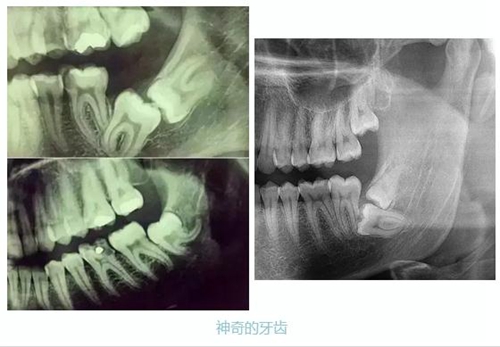

牙齒的牙根是埋在牙槽骨中的,醫(yī)生沒有透視眼,為了解患牙的牙根的形態(tài)、走向、長度及根尖周有無病變及病變大小,或者懷疑有肉眼無法確認(rèn)的其它牙科問題,都會(huì)建議患者去牙科的X光,甚至,口腔CT來全面性地確認(rèn)問題,以訂定合適的治療計(jì)劃。